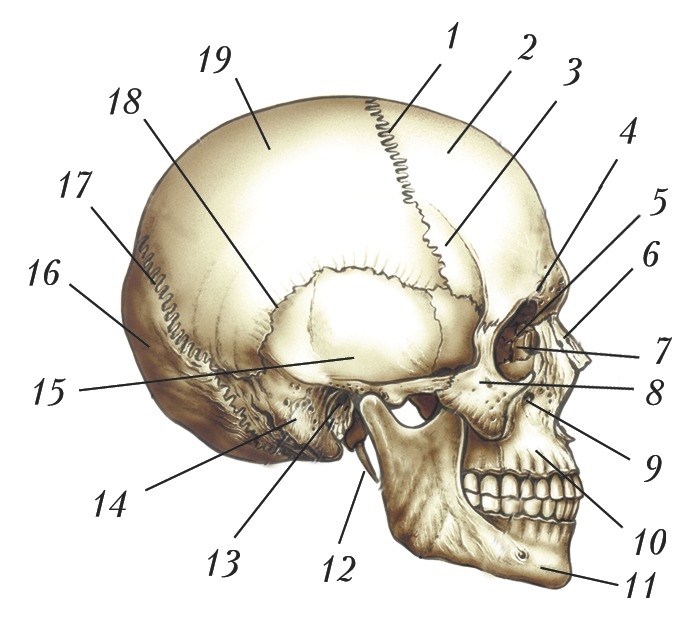

Анатомические изображения срединной сагиттальной линии черепа